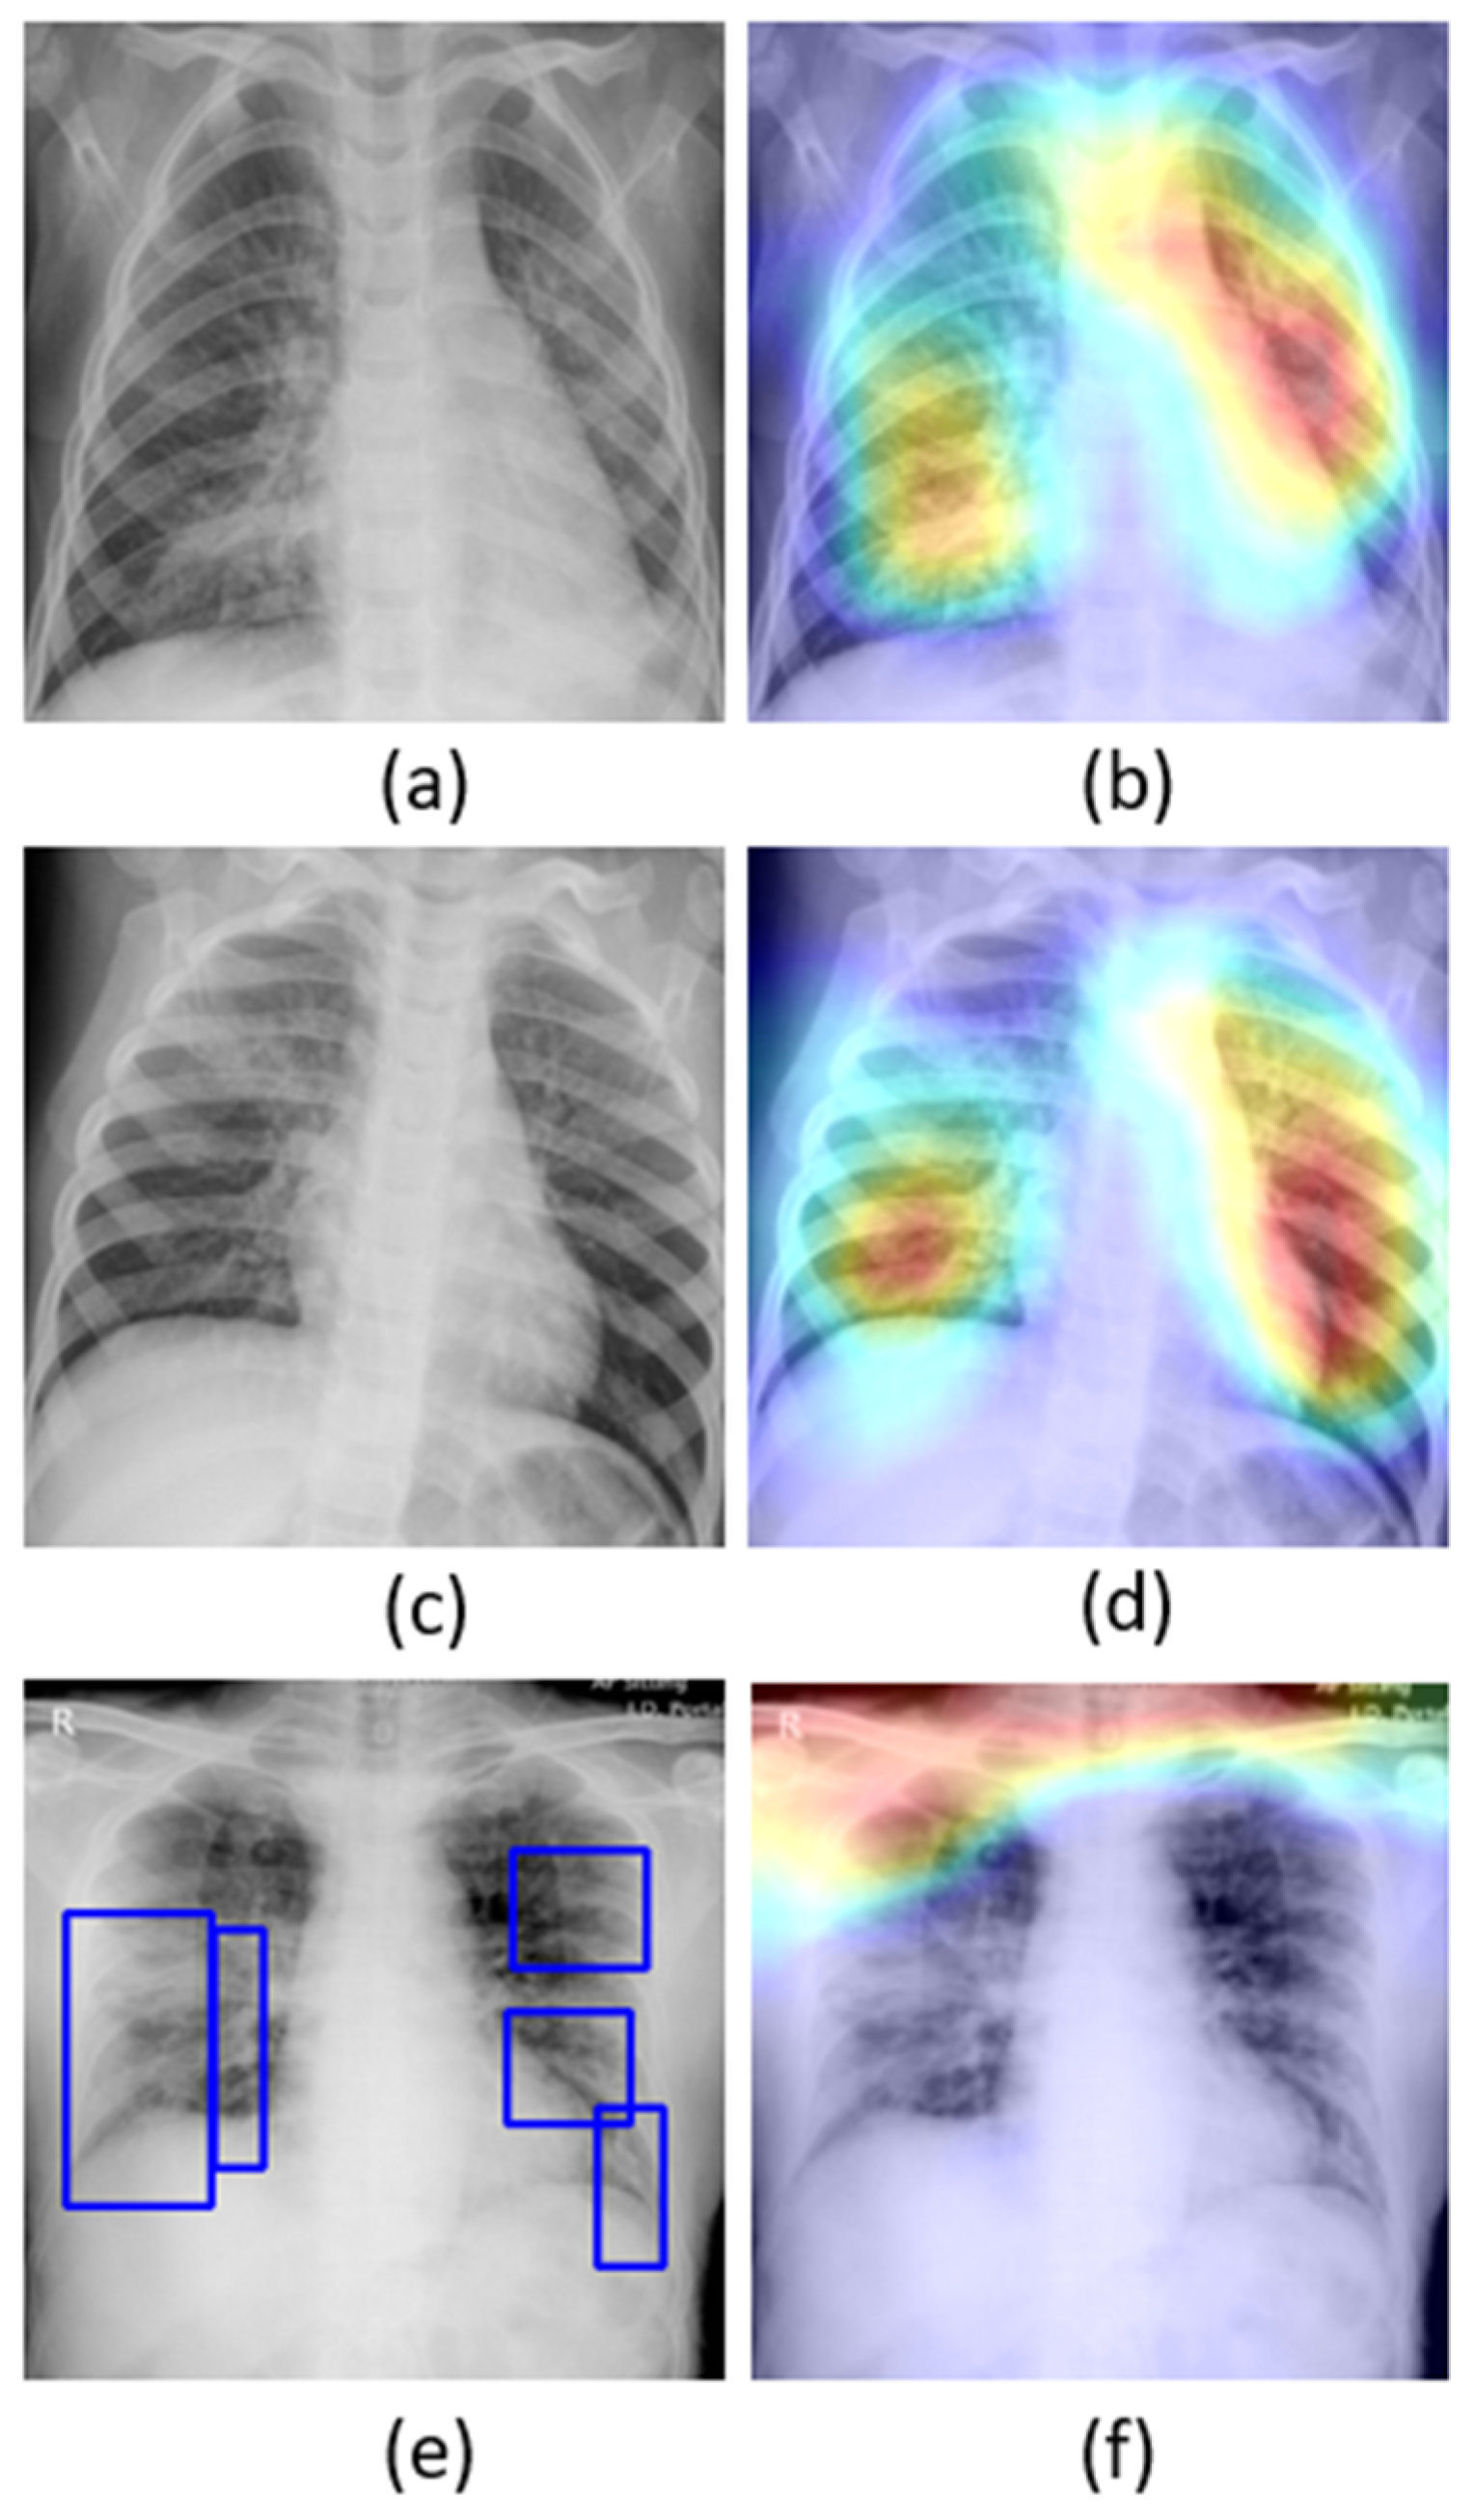

A study of the literature shows that individuals suffering from COVID-19 disease commonly present with hyperthermia and difficulty with breathing. The disease manifests in the lungs as ground-glass opacities, with peripheral, bilateral, and predominant basal distribution [2]. These patterns are visually similar to, yet distinct from, those caused by non-COVID-19-related viral pneumonia and those caused by other bacterial and fungal pathogens [2]. Further, the current literature studies revealed that it is difficult to distinguish viral pneumonia from others caused by bacterial and fungal pathogens [4]. Figure 1 shows instances of chest X-rays (CXRs) of clear lungs, bacterial pneumonia, and COVID-19-related pneumonia, respectively.

Figure 1. Chest X-rays (CXRs) showing (a) clear lungs; (b) bacterial pneumonia infection manifesting as consolidations in the right upper lobe and retro-cardiac left lower lobe; and (c) COVID-19 pneumonia infection showing bilateral manifestations. Blue frames in (c) denote radiologist annotations indicating disease regions, which serve as ground truth in our analysis.